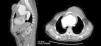

O paciente foi submetido à angiotiomografia de tórax (Figura 2) que revelou significativa lesão aneurismática comprometendo o segmento ascendente da aorta torácica e arco (medindo aproximadamente 12×93mm e com importante alargamento do mediastino ântero‐superior) e sinais de rotura, evidenciada por extravasamento de conteúdo hipodenso extratorácico e abaulamento cístico do tórax. Evidenciava‐se ainda trombo parietal com espessura de 24mm. O aneurisma ocasionava compressão significativa sobre o tronco da artéria pulmonar, rechaçando‐o posteriormente.